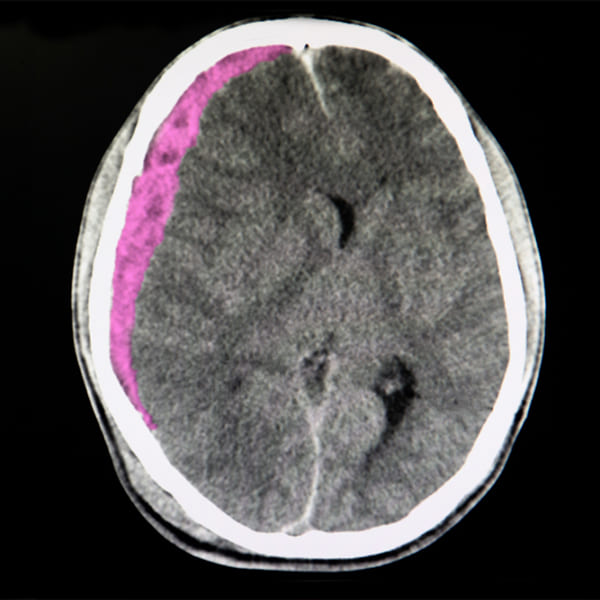

Hematomas subdural y epidural

Un hematoma subdural o epidural espinal es una acumulación de sangre en el espacio subdural o epidural que puede comprimir mecánicamente la médula espinal.

El diagnóstico se realiza con una RM o, cuando no se encuentra fácilmente disponible, con una mielografía por TC. El tratamiento se efectúa con drenaje quirúrgico inmediato.